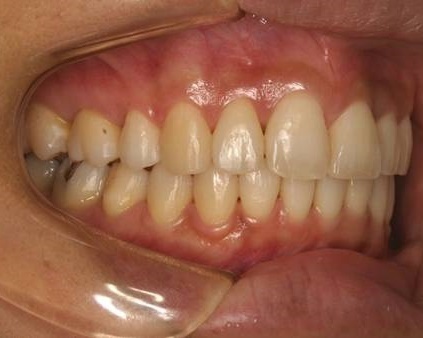

Case 2

主訴:  噛みにくい

診断:  アングルⅠ級 叢生

治療方針:

患者さんは26歳の女性で、上下顎の叢生による審美障害と咬合異常を訴えた。セファロ分析の結果、U-1 to FHおよびL-1 to Mandibularは1S.D.を超えて小さい値であった。その為、上下顎の叢生量は大きいが、上下前歯部の舌側傾斜による口元の落ち込みを防止する目的で、非抜歯で治療を行うことにした。

治療期間: 1年4カ月

費用:

診断費30000円、装置費用600000円、保定装置費用50000円、月1回の調整費4000円  (全て税別)

【 治療前 】

【 治療後 】